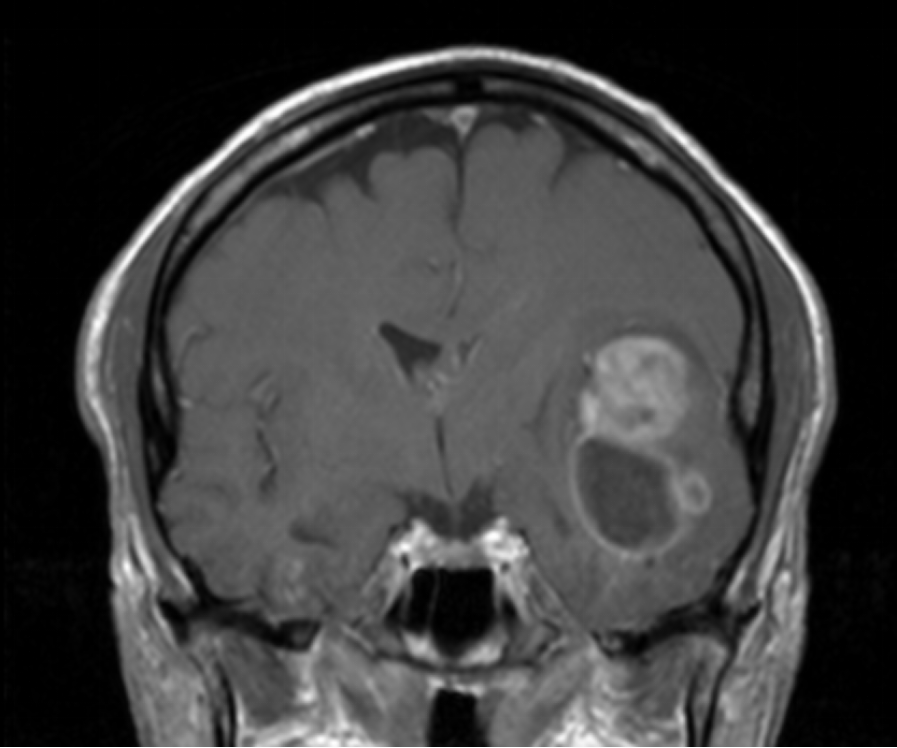

Το δόγμα της σύγχρονης χειρουργικής όγκων απεικονίζεται στις μαγνητικές αυτές. Στόχος μας είναι η μέγιστη δυνατή ασφαλής αφαίρεση του όγκου. Δεν πρέπει να στοχεύουμε στην εξαίρεση όχι μόνο του όγκου, όπως φαίνεται στην μαγνητική αλλά και στην αφαίρεση και της διηθητικής ζώνης και της υγιούς περιβάλλουσας περιοχής αν αυτή δεν έχει λειτουργίες. Η εικόνα 1α είναι προεγχειρητική, εδώ έχει σχεδιασθεί το εύρος της στοχευμένης εξαίρεσης. Η εικόνα 1β δείχνει το μετεγχειρητικό αποτέλεσμα μιας υπερολικής εξαίρεσης. Πρόκειται για την πρώτη ασθενή που χειρουργήθηκε στην Ελλάδα από τον Καθ. Γούσια τον Οκτώβριο του 2023, η οποία διαγνώσθηκε με την πιο επιθετική μορφή του γλοιοβλαστώματος, το λεγόμενο γλοιοσάρκωμα, η οποία 20 μήνες μετά την χειρουργική επέμβαση παραμένει χωρίς ένδειξη όγκου στην μαγνητική και το πιο σημαντικό χωρίς νευρολογικά ελλείμματα.